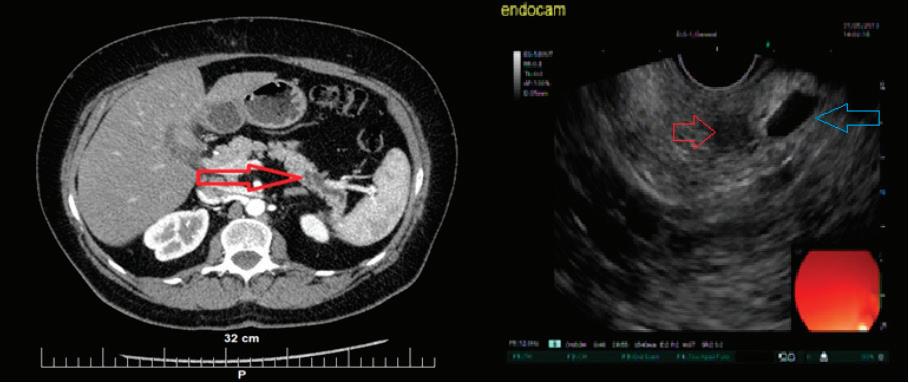

48 КИСТИ НА ПАНКРЕАСАЗНАЧЕНИЕ, ДИАГНОСТИЧНИ ДИЛЕМИ И ИНДИКАЦИИ ЗА ХИРУРГИЯ Н. Шумка, П. Карагьозов

60 РАДИОФРЕКВЕНТНА АБЛАЦИЯ НА ПАНКРЕАСНИ ТУМОРИ ПОД ЕНДОСОНОГРАФСКИ КОНТРОЛ Й. Петкова, П. Карагьозов, И. Тишков УРОЛОГИЯ

Доц. д-р Цветелина Тотомирова